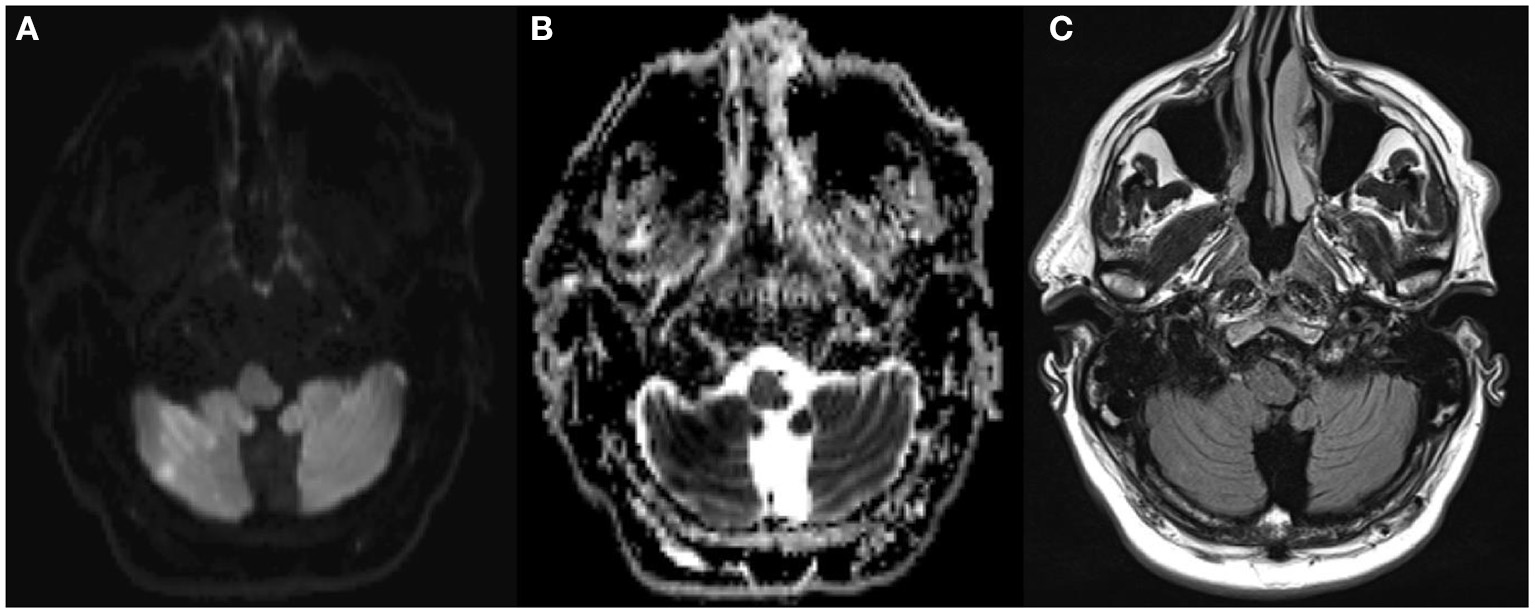

Figure 3. Fifty-five year old man with acute onset of mild dysathria and ataxia of the trunk, unable to walk (NIHSS 1). MRI showed an acute infarction [DWI positive (A), ADC negative (B), FLAIR negative (C)] in the territory of the occluded right posterior inferior cerebellar artery. The patient was treated with rtPA 3 h and 46 min after stroke onset.